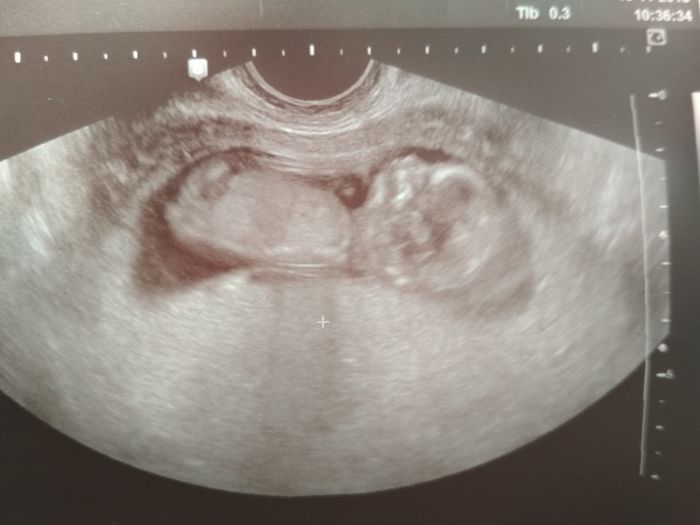

Ahoj holky, tak jsem se dočkala kontroly

doktor mi dle utz určil termín 3.6 , podle MS 5.6. Zitra jdu na screening ještě a na krev. Dnes jsem teprve dostala prukazku a řekla jsem si o fotky